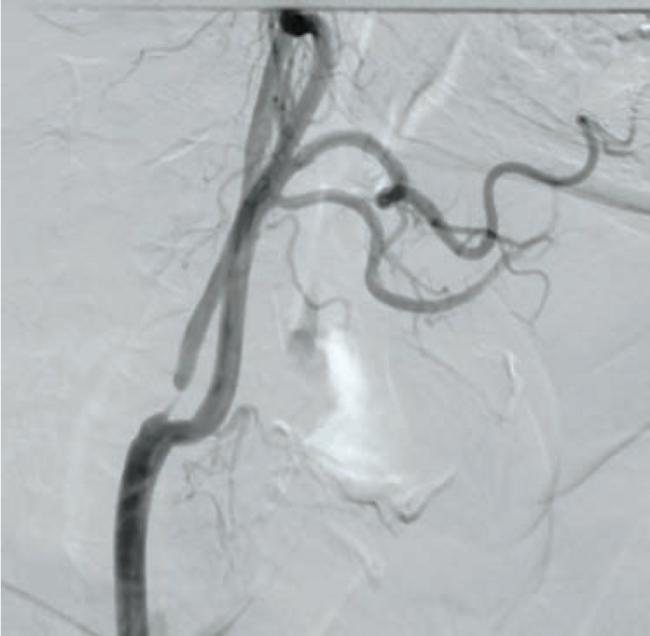

A 70-year-old hypertensive male presented with non-ST elevation myocardial infarction. Electrocardiogram showed ST depression. A complete blood count, complete blood chemistry, and PT/INR were in normal range. Lipid profile showed an LDL level of 147 mg/dl, triglycerides of 260 mg/dl, and HDL of 33 mg/dl. Coronary angiography showed triple-vessel coronary artery disease, sparing the left main stem. The patient was advised to undergo CABG surgery. During the surgical work-up, he was found to have a history of a TIA 3 months prior involving the left side of the body. Carotid Doppler showed a severe 95% ostial stenosis due to mixed plaque in the right internal carotid artery (RICA) and a mild stenosis causing 20% luminal narrowing in the left internal carotid artery. CT brain plain showed no infarction or hemorrhage. A carotid angiography and cerebral DSA showed severe stenosis at the ostium of RICA with no calcification (Figure 1). For the left ICA, both external carotid and vertebral arteries were normal. Cerebral digital subtraction angiography (DSA) showed normal intracranial circulation. A multidisciplinary approach, with a heart team including neurologists, cardiovascular surgeons, and an interventional cardiologist was adopted for this patient during the complete workup. The heart team recommended carotid revascularization prior to surgical coronary revascularization, as the patient was asymptomatic and at an intermediate risk from a coronary viewpoint. After a discussion with the patient and his family about the management options, advantages, and risks, a combined decision for CAS was made, due to its less-invasive nature as compared to CEA.

Following aseptic measures and under local anesthesia, a 7 French (Fr) right femoral access was obtained using a routine-length sheath. An .035-inch J-tip guide wire was then parked at the right common carotid artery (RCCA) using a 5 Fr Judkins right catheter, exchanged by a 7 Fr multipurpose guide. This was followed by advancement of a FilterWire EZ (Boston Scientific) across the ostial internal carotid artery stenosis, and deployed in the distal part of the extracranial ICA (Figure 2). After deployment of the FilterWire EZ, a direct stenting strategy was adopted to minimize thromboembolization. A 6 mm x 40 mm self-expanding stent was deployed at the RICA ostium (Figure 3). To our surprise, the view after stent placement showed zero flow into the distal RICA. (Figure 4) The reason appeared to be choking of the filter due to thromboembolization. The filter appeared to be overwhelmed by the volume of the debris captured. A 6 Fr Export catheter (Medtronic) was employed to suction debris from the distal ICA (Figure 5). We also administered pharmacotherapy using intra-arterial nitrate boluses and a weight-based tirofiban bolus. After these measures, there was fair flow into the distal ICA. During the period of no flow, the patient had transient hemispheric ischemic signs and an oropharyngeal airway was required, but his vitals remained stable. These symptoms rapidly resolved after establishment of ICA flow. After establishing blood flow, the proximal half of the stent that remained under-expanded was post dilated using a 4.5 mm noncompliant balloon at 12 atmospheres (Figure 6). Post dilatation, the angiographic view demonstrated good stent expansion and adequate distal flow (Figure 7). The distal protection device was then successfully removed using its retrieval sheath. The final DSA angiogram revealed excellent flow into the distal carotid (Figure 8A) and intracranial vasculature (Figure 8B), confirming no intracranial embolization. The guide was then safely removed over the .035-inch guide wire.